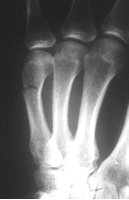

Schaftfraktur des 5. Mittelhandknochen durch schlag. Der Patient hat eine Nickelallergie. Hier wird die Fraktur in i.V. - Anästesie reponiert und mit einem 2mm Titandraht stabilisiert. Diese Versorgung ist stabil genug für eine frühfunktionelle Behandlung. Vorteil ist auch hier, dass es nicht zur Bewegungsbehinderung im Grundgelenk kommt.